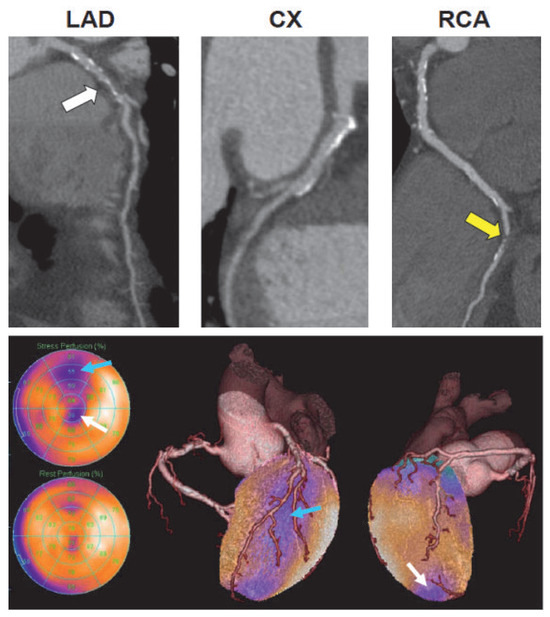

Kardiale Hybrid-Bildgebung in der Diagnostik der koronaren Herzerkrankung

by Oliver Gaemperli and Philipp A. Kaufmann

CT coronary angiography and myocardial perfusion scintigraphy are both established non-invasive techniques for the diagnosis of coronary artery disease (CAD). Cardiac hybrid imaging consists of the combination (or “fusion”) of both modalities and allows obtaining complementary morphological (coronary anatomy, stenoses) and functional (myocardial [...] Read more.

CT coronary angiography and myocardial perfusion scintigraphy are both established non-invasive techniques for the diagnosis of coronary artery disease (CAD). Cardiac hybrid imaging consists of the combination (or “fusion”) of both modalities and allows obtaining complementary morphological (coronary anatomy, stenoses) and functional (myocardial perfusion) information in a single image. The appropriate clinical use of hybrid imaging requires its integration into joint clinical diagnostic services where experts in all fields (cardiology, radiology, nuclear medicine) collaborate and colleagues with clinical and technical expertise together can exploit the potential of the new technique. The feasibility and clinical value of hybrid imaging has been documented in small cohort studies and selected series of patients. The incremental value of the hybrid technique arises from the spatial coregistration of perfusion defects with coronary stenoses. This allows to assess the haemodynamic relevance of coronary stenoses and determine the need for revascularisation procedures in each individual artery. The combination of the (native) coronary artery calcium score scan with MP-SPECT can also be helpful in different clinical scenarios. Thus, it can be anticipated, that the ongoing efforts to reduce radiation exposure and the increasing clinical interest will further pave the way for an ever increasing use of cardiac hybrid imaging in clinical practice. Full article

Figure 1